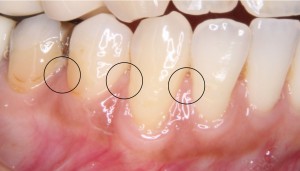

※歯肉退縮を認める歯の歯間乳頭の状態

根面被覆術の適応を判断するための診査について

歯ぐきが下がった部分に対して行う根面被覆術では、治療が可能かどうかを判断するために、いくつかの診査基準が用いられます。

これらの分類では、特に次の2つの部分の状態を確認することが重要になります。

-

歯と歯の間の歯ぐき(歯間乳頭)

歯ぐきと粘膜の境目(歯肉歯槽粘膜境)

歯と歯の間の歯ぐきの状態が重要です

根面被覆術では、歯と歯の間の歯ぐき(歯間乳頭)がどの程度保たれているかが、治療の結果に大きく関係すると考えられています。

今回の症例の診査結果

今回の患者様のケースでは、術前の診査および写真の確認から、

歯周組織の状態

が比較的良好に保たれている状態でした。

つまり、歯と歯の間の歯ぐきがしっかりと存在しており、健康的な形態が維持されている状態でした。

このような場合には、根面被覆術による改善が期待できる可能性があるため、次のステップとして治療計画を立てていきます。